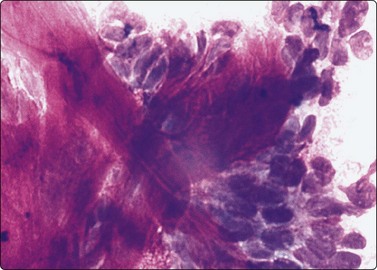

image image image image

Fig. 4.2 Cystically degenerate metastasis of well-differentiated squamous carcinoma

(A, B) Exfoliating atypical cells of ‘parakeratotic’ type in FNB smear and corresponding tissue section; (C, D) Other example with predominance of anucleate keratinized cells and clumps of keratin in the cyst lumen.

The diagnostic difficulties are due to the fact that squamous epithelial cells aspirated from a cystic metastasis of well-differentiated SCC are often anucleate or of parakeratotic type with a mature cytoplasm and a small pyknotic nucleus appearing cytologically bland, while inflammation of a benign cyst can result in immature squamous metaplasia and worrying cytological atypia. Figures 4.1 and 4.2 compare cells exfoliating from the lining of inflamed branchial cysts with those from cystic SCCs seen in histological sections. Helpful clues are that material sampled from a cystic SCC is more obviously necrotic than inflammatory, and a careful search usually reveals a few squamous epithelial cells with malignant nuclear features or abnormal keratinised cells with bizarre, globoid shapes and dense orangeophilic (Pap) cytoplasm. The nuclear atypia and hyperchromasia seen in squamous cells from a benign cyst is of degenerative type. But the distinction is not always easy (see Figs 4.1C and D). In some cases, the FNB can only be reported as indeterminate. The only ancillary test we have found useful in this setting is HPV DNA sequencing. Occult tonsillar carcinomas and other oral cavity carcinomas with cystic lymph node metastases are a common clinical problem. Many such carcinomas contain HPV DNA as evaluated by PCR or other molecular testing and a positive result in an FNA sample is strong evidence that a lesion is metastatic carcinoma rather than a branchial cleft cyst or other benign cyst.